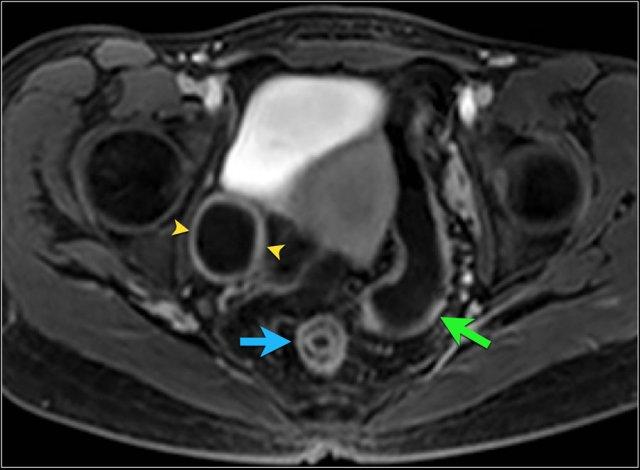

Kiểu ngấm thuốc phân lớp tại trực tràng kèm một ít mờ mỡ xung quanh trên hình ảnh T1 axial sau tiêm thuốc tương phản từ (mũi tên). Tình trạng viêm liên tục với kiểu ngấm thuốc đồng nhất có thể thấy tại đại tràng sigma (mũi tên xanh lá). Ngoài ra, có một nang phần phụ bên phải với viền ngấm thuốc (đầu mũi tên).

Kiểu ngấm thuốc

phân lớp

Kiểu này gợi ý hoạt động bệnh nặng hoặc bệnh mạn tính kéo dài (4,5).

Hình ảnh ba lớp được tạo ra do niêm mạc và thanh mạc ngấm thuốc mạnh trong khi lớp giữa không ngấm thuốc, bao gồm lớp dưới niêm mạc và lớp cơ.

Lớp giữa này có thể chứa mỡ, phù nề hoặc mô xơ.

Có thể phân biệt các thành phần này bằng chuỗi xung T2 có fat-sat.